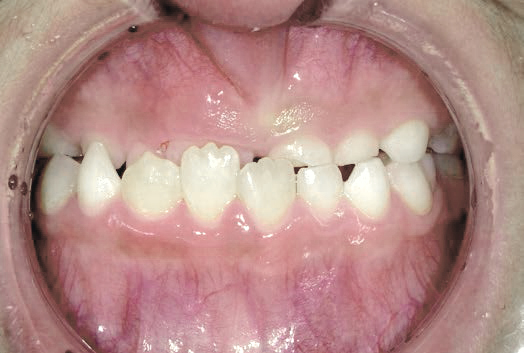

出っ歯

「本当に永久歯を抜かずに治るの?」半信半疑で相談に来られました

Mさん (矯正開始時:8歳)

Before

After

これから生えてくる永久歯のスペースがなく、歯が並ぶ余地がほとんどありませんでした。

さらに、上からあごの骨を見たところ、中央がくびれた“ひょうたん型”に変形しており、あごの成長にも偏りが見られました。

診断の結果、前歯の中心も少し左にずれており、特に犬歯が生えるスペースが足りない状態でした。

飲み込むときに下くちびるに力が入り、顔の左側にゆがみが出ている様子も確認できました。

治療を終えて

犬歯が歯ぐきの中に埋まっていたため、透明のマウスピース型装置で生えるスペースを作り正しい位置に導きました。もちろん抜歯せずに歯並びを整えることができました。お口の中がとても小さく、型どりの際にオエッとなる反応が強く、当時は装置を作るのが大変でした。しかし現在では3Dスキャナーと3Dプリンターを活用しスムーズに治療できます。

主訴・治療内容 「あごが小さいから、歯がきれいに並ばない」と他院で言われ永久歯を抜く矯正をすすめられていました。

本当に非抜歯で治療できるのか心配されていましたが、治療方法を丁寧にご説明し、お任せいただきました。

治療期間 5年

費用 550,000円(税込)